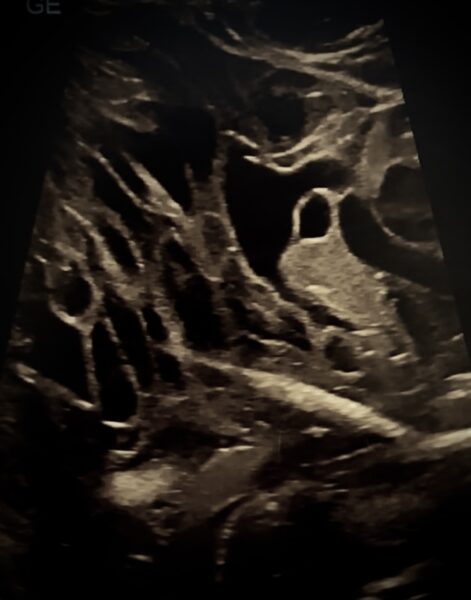

Płyn w tkankach jamy ciała u żółwia żółtolicego